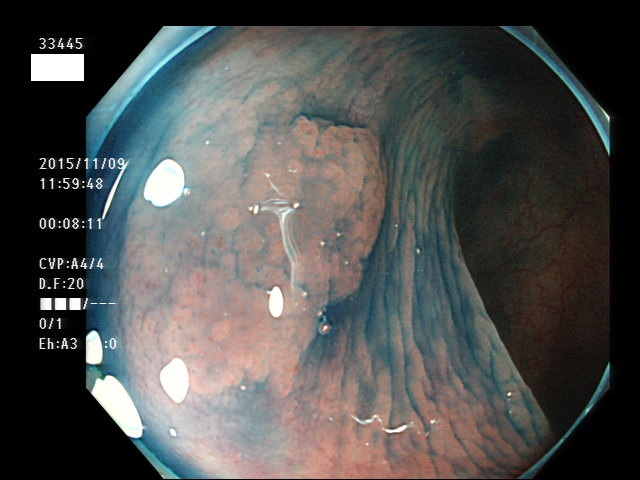

上記100名より抽出した平坦・陥凹型腺腫(=癌化の危険が高いが見落としやすい病変)の内視鏡写真